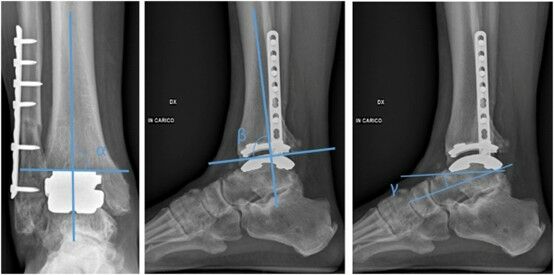

陳彥宇醫師進一步指出,「人工踝關節置換手術可分為前開式、側開式,使用不同款式的人工踝關節,適用族群也有些不同。若患者年紀較輕小於60歲左右,通常醫師會建議考慮側開式踝關節置換。因為相較於前開式踝關節置換,側開式踝關節置換在手術過程中可以保留較多骨頭,依目前人工踝關節的平均壽命10-15年來計算,假設患者在75歲以上時需要接受二次手術,保留較多骨頭對於二次手術較為有利」。

「另一個比較適合側開式踝關節置換的族群,則是腳踝受過傷、前側曾經開過刀的患者,因為腳踝前方皮膚較薄、神經血管多,傷口癒合及神經血管受傷風險較高,若患者腳踝曾受傷,傷口疤痕又剛好在腳踝前方,同位置再開一次刀,可能提高傷口癒合風險,只是這個部分還是要尊重各個主治醫師的專業判斷」,陳彥宇醫師補充。

側開式踝關節置換手術,資料來源:https://link.springer.com/article/10.1186/s12891-019-2503-6